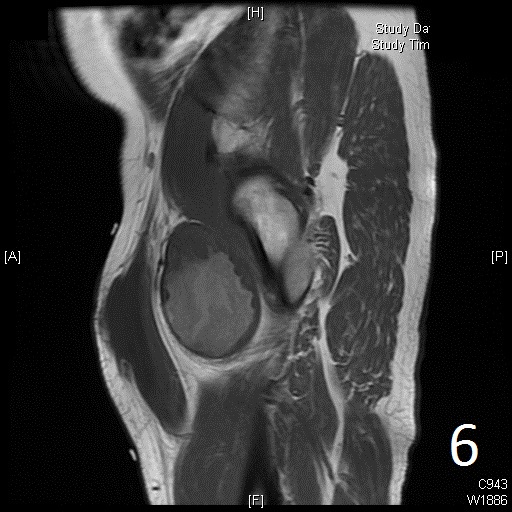

• 60% of fibrosarcomas are intramuscular (Fig. 2, 3, 5, 6, 7, 8)

• On gadolinium, viable areas of tumor enhance, while areas of significant necrosis and hemorrhage do not enhance (Fig. 6).

Fig. 5-9: Axial and sagittal (Fig. 6) MRI shows a fibrosarcoma in the proximal quadriceps muscle that is isointense to muscle on T1W images, and a heterogeneous on T2W FS (Fig. 7, 8). The patient was treated with preoperative chemotherapy and the mass underwent extensive necrosis. The mass does not show any enhancement with contrast due to the extensive necrosis. There is only peripheral enhancement with contrast on T1W FS (Fig. 9).